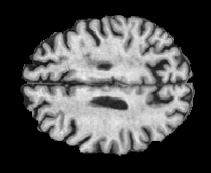

In order to analyze qualitatively the results of our generator, we extract slices with different WMHs loads, Table 4 shows the reconstruction results for three different levels of loads. As we can see in the first row, both methods produce a similar response in regions with a low load of lesions, it can be observed that generated images are similar to the real FLAIR images in the left, and these not present evident structural distortions. However, it can be noted images exhibit blurred effects, which can be due to L2 based optimization, more complex generative networks with adversarial loss optimization as GANs tend to eliminate blurred effect but at the expense to produce structural distortions. In the application presented in this work it is important to preserve the structural information, thus, our L2 based optimization present a good balance between preserve structural information and blurred effects. In the second and third column, it can be observed the performance of both methods when facing the presence of lesions, as can be seen, both methods have a good response to large and contiguous lesions. It also can be noted both methods tend to produce poor performance in small and diffuse WMHs marked in red, note, these lesion do not exhibit identifiable patterns in T1 images, however it can be seen that our proposed method is more sensitive to these patterns which enable to highlight some small regions as those marked in green.

FLAIR T1 Offline synthesis Proposal

Table 4: Results of Generation for all the proposed methods,